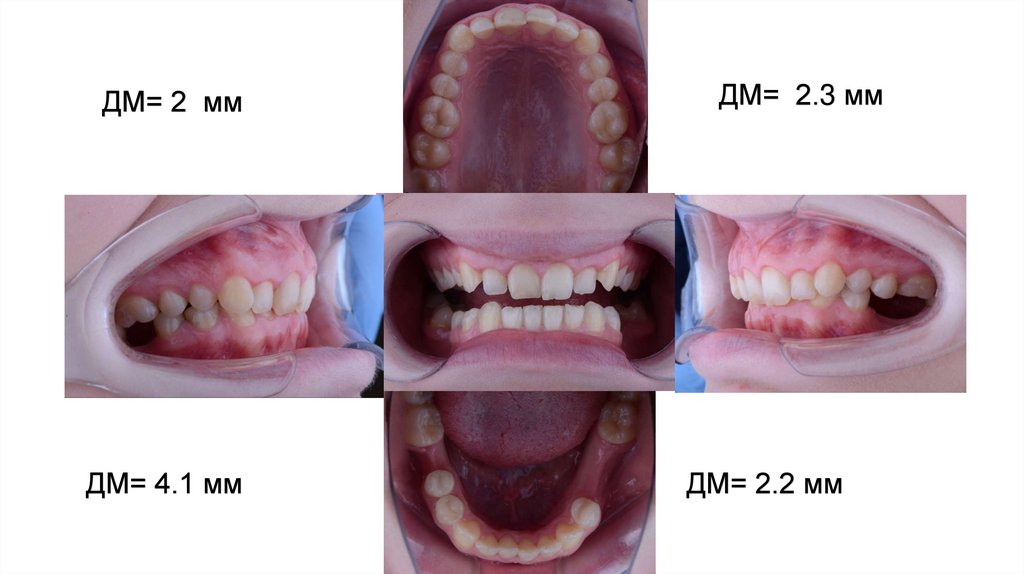

Соотношение резцов в сагиттальной плоскости (OJ) - 2 мм

2 класс по Энгля 4.3 мм ПО КЛЫКАМ

2 класс по Энгля 4.6мм

ДМ= 2 мм

ДМ= 4.1 мм

ДМ= 2.3 мм

ДМ= 2.2 мм